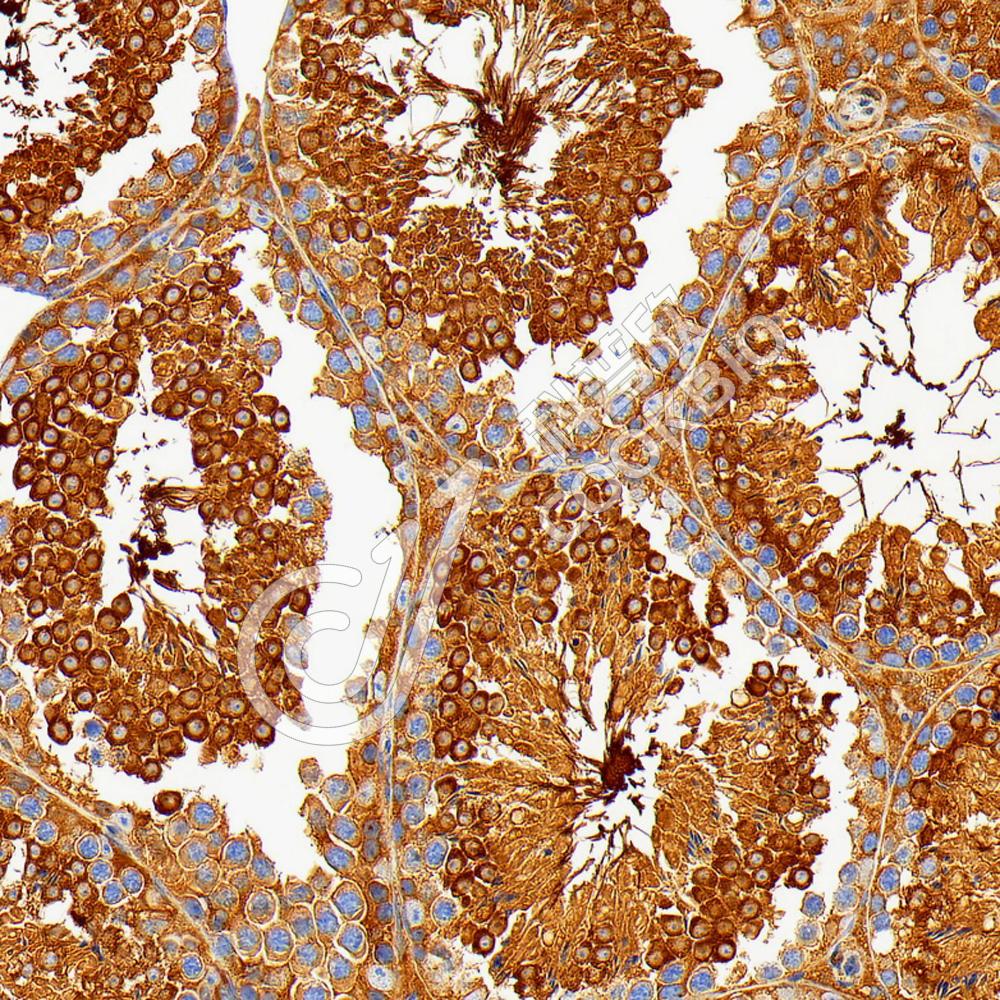

IHC检测PKA alpha蛋白(货号 K5450153).

样品: 人食管癌, 4%多聚甲醛 (货号KSG1101) 固定12-24小时.

抗原修复: 柠檬酸抗原修复液(干粉, pH 6.0) (KSG1201), 高压锅均匀喷气计时2分钟.

—抗: 1: 3300稀释, 4℃ 孵育过夜.

二抗: S-vision免疫组化多聚二抗(山羊抗兔),即用型 (货号KB3906), 室温孵育20分钟.